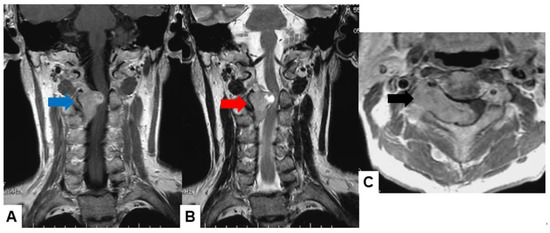

Meningiomas usually indicate isointensity in both T1- and T2-weighted MR imaging and are enhanced homogeneously (Figure 3) [35]. Meningiomas are sometimes calcified and are recognized in CT (Figure 4). The key points of a differential diagnosis of meningioma and schwannoma are in Table 4.

Figure 3.

Forty-two F, spinal meningioma. (A) T1-weighted midsagittal image, (B) T2-weighted midsagittal image, and (C) enhanced T1-weighted midsagittal image. (D) CT. Red arrows indicate tumor and blue arrow shows tumor enhancement. Yellow arrow shows dural tail sign and black arrow indicates tumor ossification.